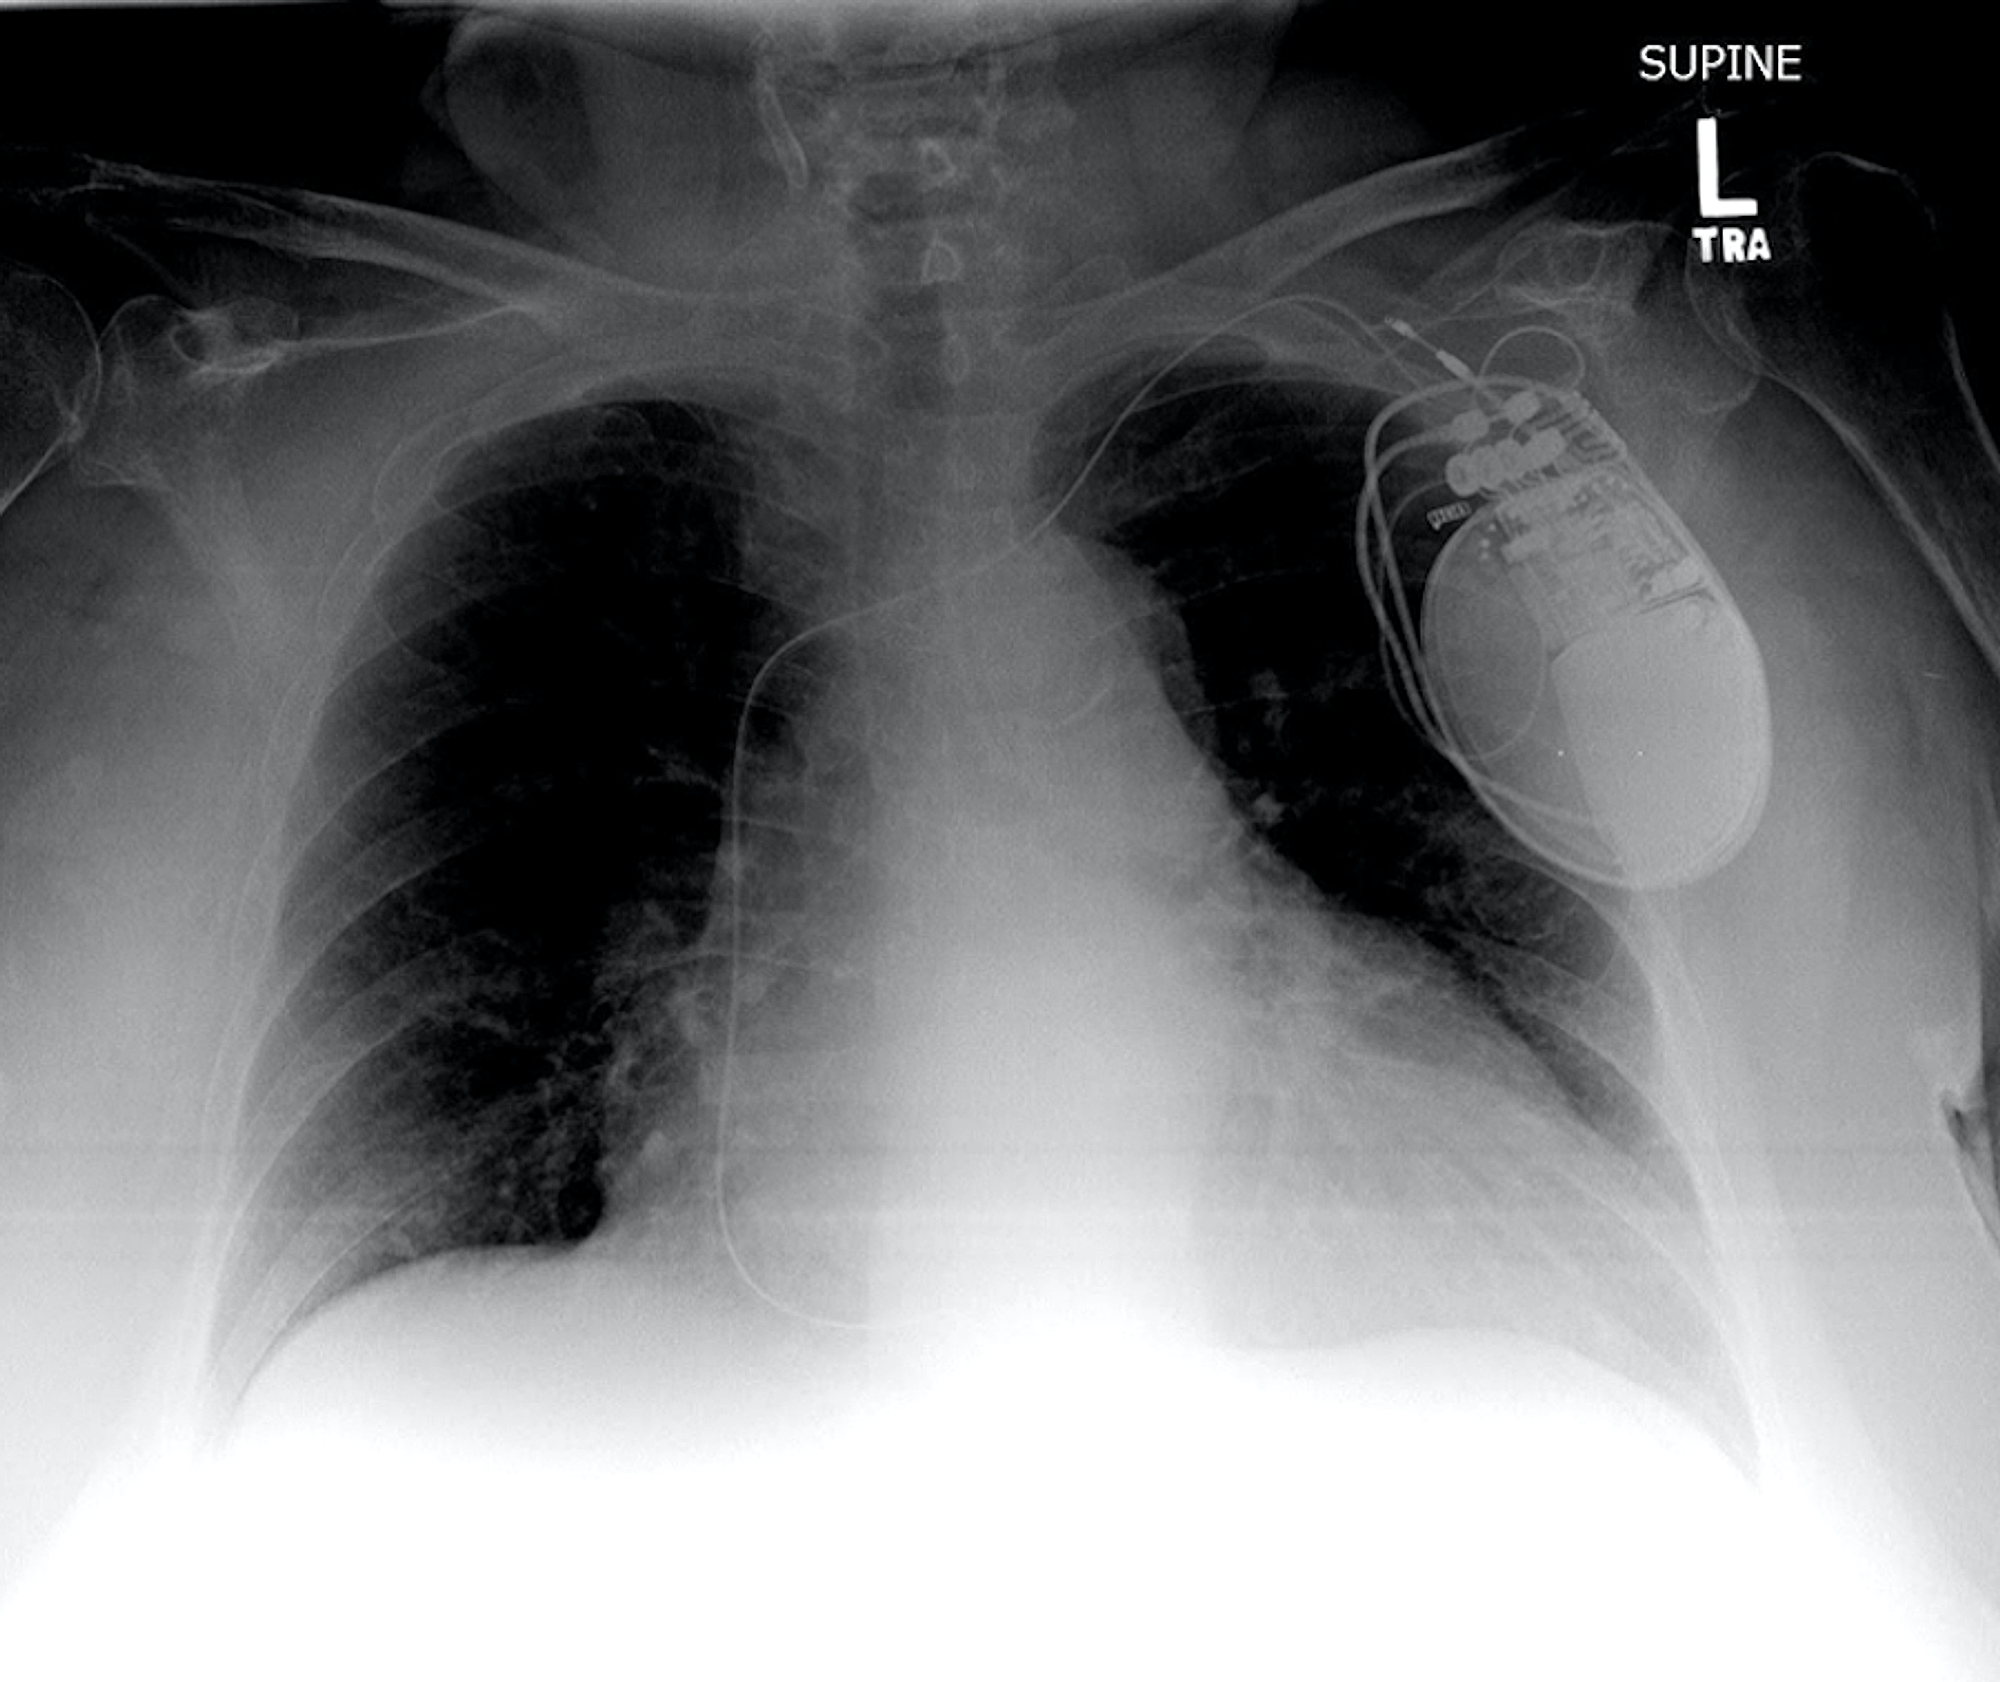

From www.ajronline.org

Radiography of Pacemakers and Implantable Cardioverter Defibrillators AJR Defibrillator Implant Of Pacemaker It is similar to a. an implantable cardioverter defibrillator (icd) looks similar to a pacemaker, though slightly larger. When your heartbeat is too. an implantable cardioverter defibrillator (icd) is a medical device that monitors your heart and manages heart rate when needed. it detects and stops irregular heartbeats, also called arrhythmias. It means that your heart beats. Defibrillator Implant Of Pacemaker.